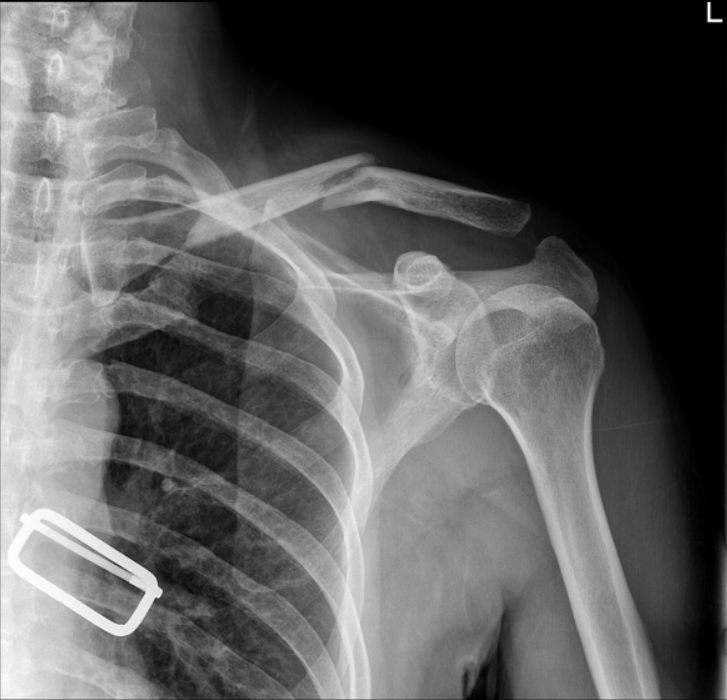

急诊就诊3天后门诊随访x线片显示锁骨中轴骨折倒v型移位